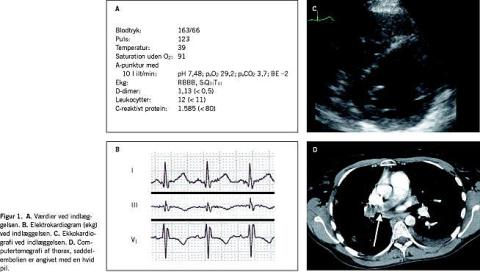

En 32-årig kvinde fik åndenød, hoste og smerter i thorax under boldspil. Antibiotika havde kun kortvarig effekt, og patienten blev henvist til et lungemedicinsk ambulatorium. Ved en spirometri påviste man let obstruktiv lungefunktionsnedsættelse, og der blev indledt behandling med β -agonist og prednisolon. Ved røntgen og computertomografi (CT) af thorax påviste man bilaterale lungeinfiltrater, som fluktuerede over tid. Undersøgelser for reumatologisk sygdom gav negativt resultat. En lungebiopsi var ikke diagnostisk, og hun blev henvist til torakoskopisk biopsi, men forinden tilstødte der i ottende sygdomsmåned akut indlæggelseskrævende forværring med stærke, respirationssynkrone brystsmerter. Patienten var respiratorisk påvirket og højfebril, og biokemisk var D-dimer, leukocytter og C-reaktivt protein forhøjede (Figur 1A ). Et elektrokardiogram (ekg) viste sinustakykardi med højresidigt grenblok og SI QIII TIII -mønster (Figur 1B ). Ved ekkokardiografi blev der fundet D-formet venstre ventrikel, paradoks bevægelse af det interventrikulære septum og dilatation af højresidige kamre (Figur 1C ). Ved spiral-CT af thorax påviste man saddelembolus i truncus pulmonalis (Figur 1D ), mens en ultralydundersøgelse af underekstremiteter og bækken viste normale forhold.